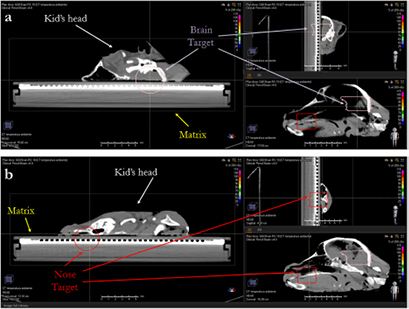

Figure 8 presents the plan optimized and calculated with the PB algorithm for the brain target of the lamb's head with a gantry angle of 0° and the RS 30 cm from the isocenter. MC recalculation shows significant differences in the dose volume histogram (DVH) and mostly located in the distal part of the target.

Figure 8. PB optimized dose distribution on the brain target of the lamb head (top left) and MC recalculation (middle left) with a proton field angle of 0° and the RS 30 cm from the isocenter (i.e. air gap ~20 cm). The white lines represent the dose profiles' (bottom) extraction plans. On the right side of the figure, the DVHs of both dose distributions (top right) and dose difference (middle right) are displayed.

Download figure:

Standard image High-resolution imageFrom the MatriXX measurements, it is clear that the PB algorithm over-estimates the target coverage (figure 9) and also in the case of small air gaps (i.e. RS 18 cm from the isocenter) the PB γ passing rate is <90%; the splitting technique improves the agreement between the measurements and the calculation performed with the PB dose engine (table 3).